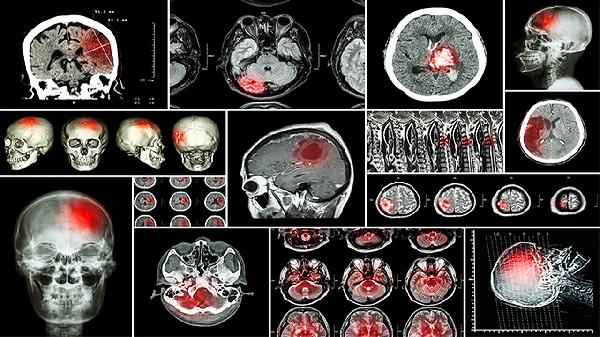

益智康脑丸主要用于治疗脑供血不足、脑动脉硬化、血管性痴呆等脑血管疾病,也可用于改善脑外伤后遗症、阿尔茨海默病等引起的记忆力减退和认知功能障碍。

1、脑供血不足

2、脑动脉硬化

3、血管性痴呆

4、脑外伤后遗症

5、阿尔茨海默病